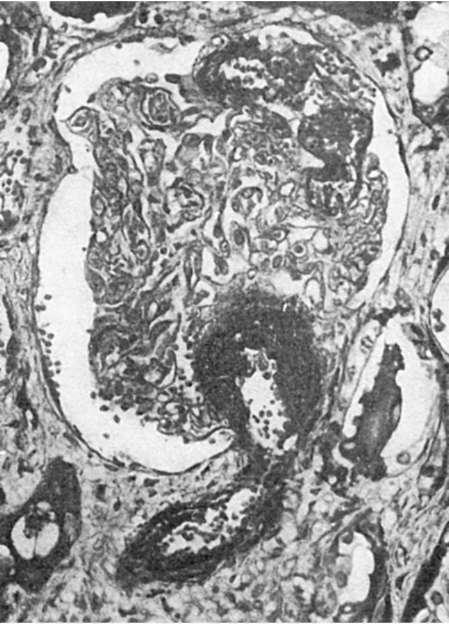

Рис. 152. Фибриноидный почки (участки некроза

черные)

своеобразным расположением его в виде частокола, что является выражением спазма артериолы (рис. 151),плазматическим пропитыванием или фибриноидным некрозом ее стенки (рис. 152) и присоединяющимсятромбозом. В связи с этим развиваются инфаркты, кровоизлияния. В настоящее время злокачественная гипертония встречается редко, преобладает доброкачественно и медленно текущая гипертоническая болезнь.